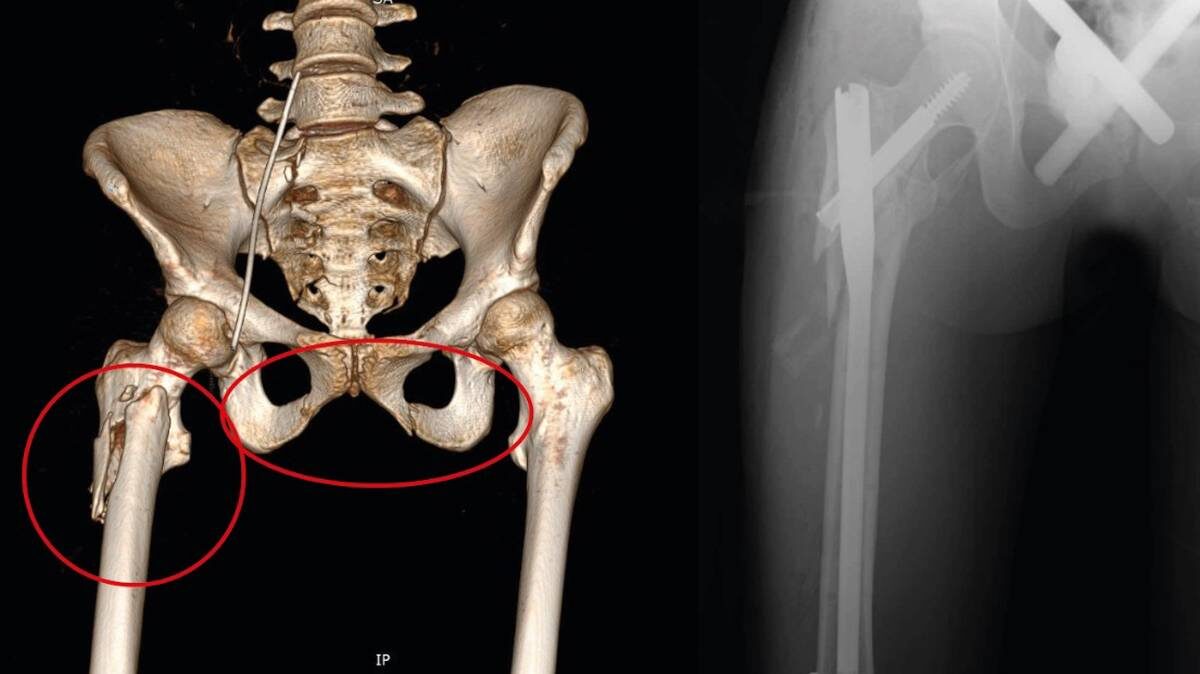

В подмосковном Сергиевом Посаде 18-летняя девушка выжила после падения с девятого этажа. Доктора диагностировали у нее черепно-мозговую травму, закрытое повреждение грудной клетки с поражением легких, а также переломы костей таза и бедра и травму живота. Об этом в четверг, 25 сентября, сообщили в пресс-службе Сергиево-Посадской больницы. После прибытия в медучреждение пострадавшую в крайне тяжелом состоянии сразу же направили в реанимацию — она потеряла много крови и находилась в коме. Медики оперативно начали переливание, ввели антибиотики, дренировали легкие и наложили аппараты внешней фиксации на переломы. Уже через несколько дней девушка пришла в себя, а спустя еще две недели она смогла отправиться домой. — На данный момент пациентка дома. В ближайшее время ее ждет большой курс реабилитации, после которого она сможет вернуться к привычному образу жизни, — передает официальная страница медучреждения в VK. Московские врачи из Детской городской клинической больницы имени Башляевой про

Фото: пресс-служба Сергиево-Посадской больницы

В подмосковном Сергиевом Посаде 18-летняя девушка выжила после падения с девятого этажа. Доктора диагностировали у нее черепно-мозговую травму, закрытое повреждение грудной клетки с поражением легких, а также переломы костей таза и бедра и травму живота. Об этом в четверг, 25 сентября, сообщили в пресс-службе Сергиево-Посадской больницы.

После прибытия в медучреждение пострадавшую в крайне тяжелом состоянии сразу же направили в реанимацию — она потеряла много крови и находилась в коме. Медики оперативно начали переливание, ввели антибиотики, дренировали легкие и наложили аппараты внешней фиксации на переломы. Уже через несколько дней девушка пришла в себя, а спустя еще две недели она смогла отправиться домой.

— На данный момент пациентка дома. В ближайшее время ее ждет большой курс реабилитации, после которого она сможет вернуться к привычному образу жизни, — передает официальная страница медучреждения в VK.